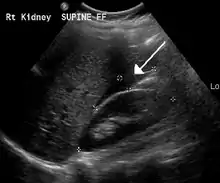

The use of ultrasound has become the standard of care when preparing a patient for paracentesis. Confirmation of an ascitic effusion reduces the risks associated with a dry or blind tap of the abdomen. Anatomic landmarks, such as the midline linea alba (abdomen) approach, were traditionally used as reference points for needle insertion. Phased array or curvilinear ultrasound transducers are typically used in the hospital and outpatient setting to identify ascites in the abdominal cavity. Fluid within the abdominal cavity appears hypoechoic or anechoic (black) on ultrasound. Morisons pouch (hepatorenal recess) is a common starting location in concordance with ultrasound FAST (Focused assessment with sonography for trauma) exam. Fluid collection can occur in a number of different locations and may be difficult to find, especially if the patient only exhibits a small volume of ascites. Measurement of the amount of fluid within the abdominal cavity is not necessary or very successful. Identification of sufficient fluid within the abdominal cavity for fluid analysis or to achieve a therapeutic benefit is all that is required to proceed to paracentesis. Ultrasound guidance of the paracentesis can also be used as an additional safety measure to ensure the needle stays within the ascitic fluid and avoidance of important vessels within the abdominal cavity. [5]